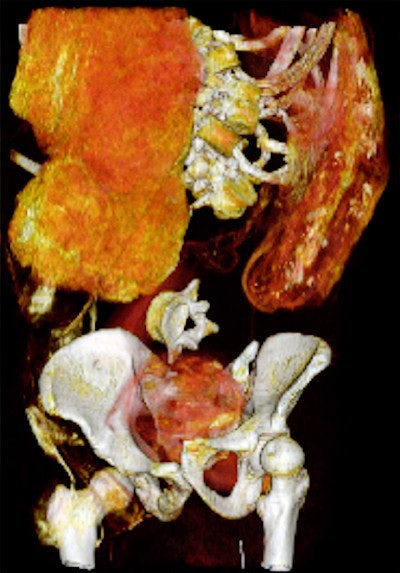

Dr. Sahar Saleem, a professor of radiology at Cairo University who specializes in CT mummy imaging, and archeologist Zahi Hawass, PhD, have used CT scans and 3D reconstructions to suggest he had multiple killers. They have presented their findings in an article published on 17 February in Frontiers of Medicine that received over 10,500 page views by February 21.

CT revealed details of the head injuries, including wounds that had not been discovered in previous examinations and had been skillfully hidden by the embalmers. The mummy's deformed hands indicate that Seqenenre may have been captured on the battlefield, and his hands were tied behind his back, preventing him from deflecting the fierce attack on his head.

The CT scans, combined with other evidence, suggest the execution was carried out by multiple attackers, which the scientists confirmed by studying five different Hyksos weapons that matched the king's wounds. The study also determined that Seqenenre was about 40 when he died, based on the detailed morphology revealed in the images, providing the most precise estimate to date, according to the authors.

Saleem examined the mummy on May 4, 2019. She said she used the usual optimum CT scan parameters, including field-of-view and slice thickness, to provide the best 3D reconstruction. Because of the COVID-19 pandemic, it took several weeks to study the Hyksos weapons stored at the Cairo Egyptian Museum and to correlate them with the injuries by physical inspection of the mummy and on CT scans.